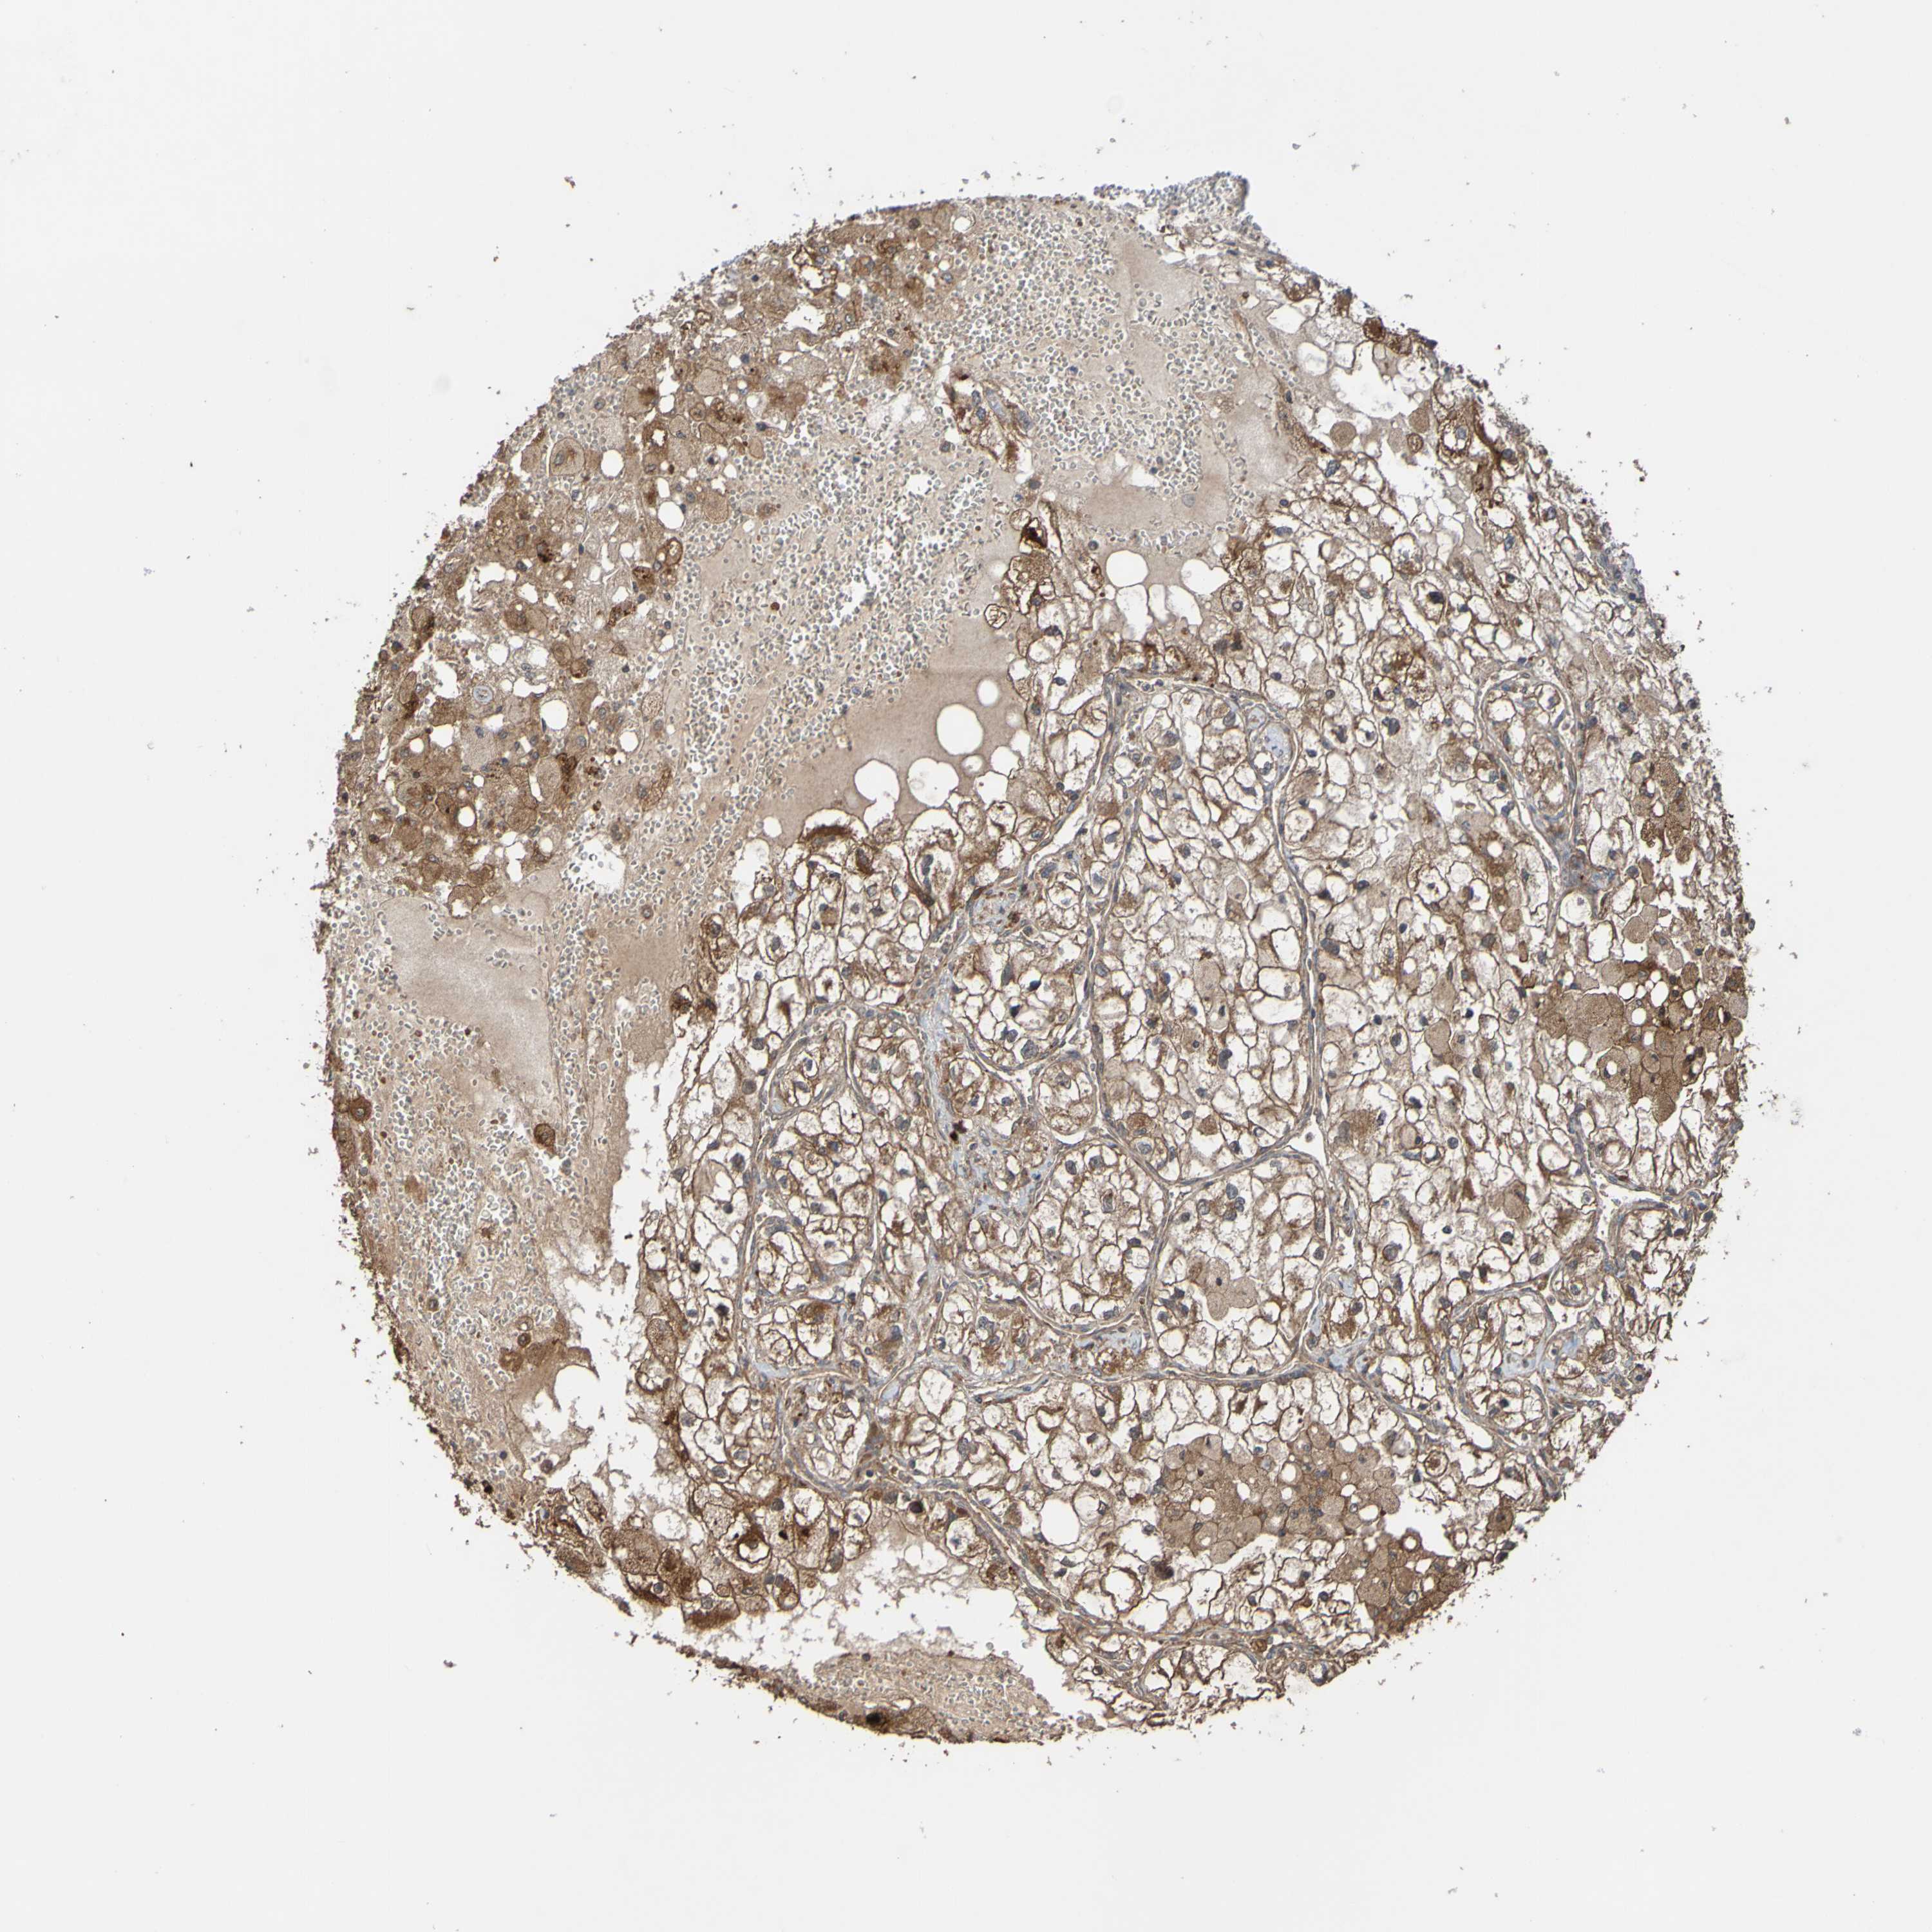

KIDNEY RENAL CLEAR CELL CARCINOMA (TCGA) - Interactive survival scatter ploti

The Survival Scatter plot shows the clinical status (i.e. dead or alive) for all individuals in the patient cohort, based on the same data that underlies the corresponding Kaplan-Meier plots. Patients that are alive at last time for follow-up are shown in blue and patients who have died during the study are shown in red.

The x-axis shows the expression levels (FPKM) of the investigated gene in the tumor tissue at the time of diagnosis. The y-axis shows the follow-up time after diagnosis (years). Both axes are complimented with kernel density curves demonstrating the data density over the axes. The top density plot shows the expression levels (FPKM) distribution among dead (red) and alive patients (blue). The right density plot shows the data density of the survived years of dead patients with high and low expression levels respectively, stratified using the cutoff indicated by the vertical dashed line through the Survival Scatter plot. This cutoff is automatically defined based on the FPKM cutoff that minimizes the p-score. The cutoff can be changed by dragging the vertical line or by entering a cutoff value in the square labeled "Current cut-off".

Under the Survival Scatter plot the p-score landscape (black curve; left axis) is shown together with dead median separation (red curve; right axis). Dead median separation is the difference in median mRNA expression between patients who have died with high and low expression, respectively. It is calculated as follows: median FPKM expression of dead patients with high expression - median FPKM expression of dead patients with low expression. This is intended to aid the user in visually exploring custom cutoffs and the associated p-scores and dead median separation.

Individual patient data is displayed and can be filtered by clicking on one or more of the category buttons on the top of the page. Categories describing expression level and patient information include: high, low, alive, dead, female, male and tumor stages. The scale of the x-axis can be toggled between linear and log-scale by clicking on the "x log" button. Mouse-over function shows TCGA ID, patient information and mRNA expression (FPKM) for each patient.

& Survival analysisi

Kaplan-Meier plots summarize results from analysis of correlation between mRNA expression level and patient survival. Patients were divided based on level of expression into one of the two groups "low" (under cut off) or "high" (over cut off). X-axis shows time for survival (years) and y-axis shows the probability of survival, where 1.0 corresponds to 100 percent.

UCN is potential prognostic, high expression is unfavorable in Kidney Renal Clear Cell Carcinoma (TCGA)

Best expression cut offi

Based on the FPKM value of each gene, patients were classified into two groups and association between prognosis (survival) and gene expression (FPKM) was examined. The best expression cut-off refers the FPKM value that yields maximal difference with regard to survival between the two groups at the lowest log-rank P-value. Best expression cut-off was selected based on survival analysis .

When clicking on this number, the vertical dashed line indicating cut-off, the interactive survival plot, and the Kaplan-Meier curve will be adjusted to show results based on the best expression cut-off.

: 2.52

TCGA RNA samplesi

RNA-seq data is reported as average FPKM (number Fragments Per Kilobase of exon per Million reads), generated by the The Cancer Genome Atlas (TCGA) .

Normal distribution across the dataset is visualized with box plots, shown as median and 25th and 75th percentiles. Points are displayed as outliers if they are above or below 1.5 times the interquartile range. FPKM values of the individual samples are presented next to the box plot.

Average pTPM 2.0

Number of samples 521